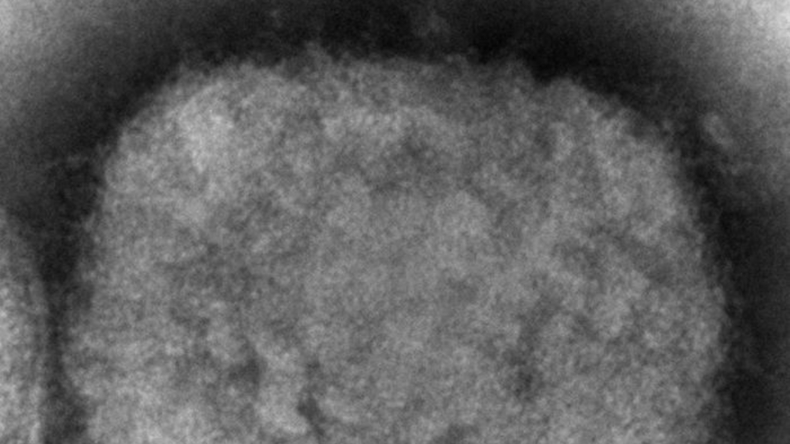

© Cynthia S. Goldsmith, Russell Regner Source: AP

Image prise au microscope électronique en 2003, montrant un virion de la variole du singe (image d'illustration).